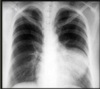

22

Q

¿Qué proyección es la siguiente?

A

PA